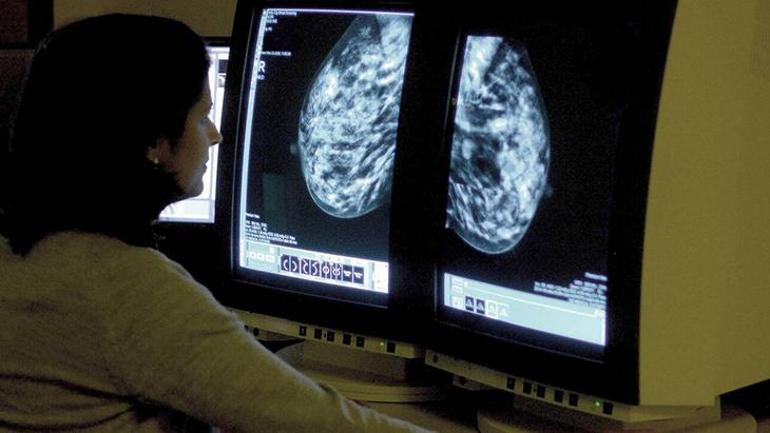

Betül Yasemin Kökbek / Milliyet.com.tr – Uzmanlara nazaran, hayatımızın büyük bir çoğunluğunu kaplayan yapay zekâ artık yalnızca bir teknolojik araç değil, radyoloji ve patoloji alanlarında tabiplerin en güçlü asistanı haline gelmiş durumda. Bilhassa mamografi manzaralarının değerlendirilmesinde yapay zekâ, gözden kaçabilecek en küçük ayrıntıları bile tespit ederek erken teşhis oranlarını artırıyor. Uzmanlara nazaran yapay zekânın asistanlığı sayesinde göğüs kanserinde erken teşhis, şahsileştirilmiş tedavi ve yüksek ömür oranı standart hale gelebilir. Bu yenilikleri klinik pratiğinde faal olarak kullanan Meme Cerrahı Prof. Dr. Fatih Aydoğan, yapay zekânın teşhisten tedaviye kadar olan süreçte nasıl devreye girdiğini ve göğüs kanseriyle uğraşta hastaların hayatını nasıl dönüştürdüğünü Milliyet.com.tr’ye olarak anlattı.

Bazı ülkelerde mamografi değerlendirmelerinin iki doktor tarafından yapıldığını, Türkiye’de birden fazla merkezde bu sürecin tek tabiple yürütüldüğünü ileten Prof. Dr. Aydoğan, bu noktada yapay zekânın adeta ikinci bir göz üzere davranarak bilhassa ağır göğüs dokusuna sahip bayanlarda küçük lezyonları yüksek hassasiyetle saptadığını ve erken tanıya katkı sağladığının altını çizdi. En şaşırtan tarafının ise yapay zekânın mamografi imgesini incelerken yalnızca göğüs kanserine odaklanmaması olduğunu belirten Prof. Dr. Fatih Aydoğan, “Aynı vakitte göğüs damarlarındaki kalsifikasyonları (kalsiyum birikmeleri) tahlil ederek, hastanın ileride kalp-damar hastalığı geliştirme riskini de öngörebiliyor. Bu da yapay zekânın sadece kanser teşhisinde değil, genel sıhhat idaresinde de yeni bir kapı açtığını gösteriyor“ açıklamasında bulundu.

“Yapılan çalışmalarda en gerçek mamografi değerlendirmesinin tabip ve yapay zekânın birlikte çalıştığı hibrit modellerle elde edildiği görüldü. Yapay zekâ sistemlerinin bilhassa ağır göğüs dokusunda gözden kaçabilecek küçük kitleleri işaretleyerek tanısal doğruluğu artırıyor. Ayrıyeten göğüs kanseri tedavi planlamasında kritik kıymete sahip HER2 (kanser hücrelerinin büyümesini destekleyen protein) patoloji testlerinde de yapay zekâ dayanaklı dijital tahlillerin hayli yararlı olduğu görülüyor.” – Prof. Dr. Fatih Aydoğan